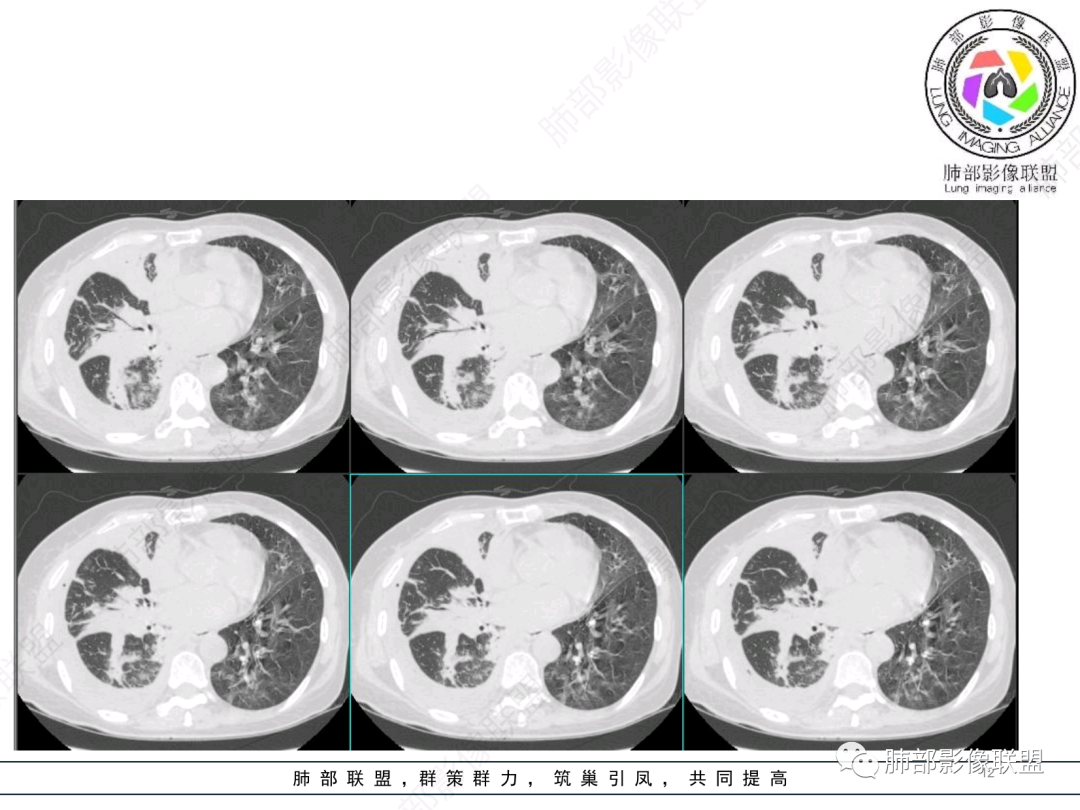

出院前复查CT:

复查左肺病灶没好转

也不符合急性炎症特点

还有一次CT:

肿瘤合并感染太有迷惑性,就这个临床症状及实验室检查,肯定考虑感染啊

针对性治疗后复查不吸收,才会想肿瘤合并

一句话的小结:

本病例之复杂,很难单单以一般临床表现或者影像学表现加以解释。

病程短,炎性指标高,缺乏先期影像学资料对比,不同病变在影像上的相互叠加等等都增添了复杂性!

责任病原菌也出乎预料,嗜麦芽窄食单胞菌及鲍曼不动杆菌感染,多见于易感人群,尤其是院内感染,譬如呼吸机相关患者。